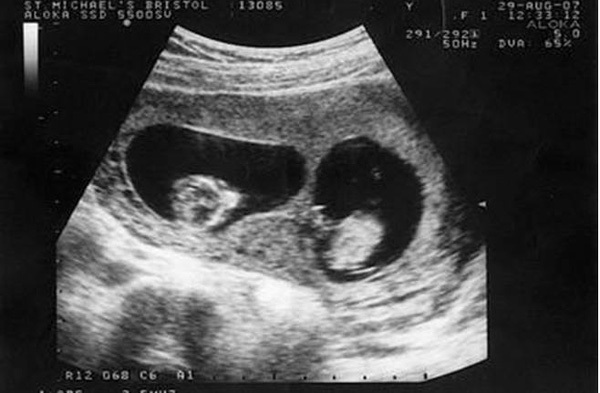

Khi mang bầu, chị Tiểu Mai và gia đình vô cùng hạnh phúc khi biết sắp chào đón cặp song sinh. Tuy nhiên, đến ngày sinh, không chỉ riêng gia đình mà đến ngay cả chị Tiểu Mai cũng cảm thấy vô cùng choáng váng khi sự thật lại không như khi siêu âm.

Trong thời kì đầu mang thai, Tiểu Mai, 25 tuổi, người Trung Quốc đi siêu âm và bác sĩ thông báo cô đang mang trong mình thai sinh đôi. Bác sĩ có dặn cô tháng sau tới siêu âm định kỳ nhưng vì bệnh viện ở xa nhà nên Tiểu Mai không tới khám lại nữa.

Trong quá trình mang thai, Tiểu Mai chỉ đi khám 3 lần và sinh con ở tuần thứ 37. Cả gia đình đều chuẩn bị sẵn tâm lý vui mừng để đón 2 đứa trẻ chào đời nhưng sau khi đưa được hai em bé ra ngoài, các bác sĩ nhìn thấy một đôi chân nữa trong bụng Tiểu Mai, họ lập tức đưa em bé thứ 3 ra ngoài trong sự ngỡ ngàng.

Trên thực tế, Tiểu Mai đã mang thai 3 đứa trẻ, 2 trai 1 gái nhưng khi siêu âm bác sĩ không hề thấy sự hiện diện của đứa trẻ thứ ba nên đã tiết lộ kết quả là sinh đôi. Họ cũng cho biết, có thể 2 đứa bé kia đã nằm chắn đứa bé này nên khi siêu âm không nhìn thấy được. Thật may mắn, đứa bé thứ 3 ra đời rất khỏe mạnh. Vậy là niềm vui của gia đình lại được nhân lên khi mà đáng lẽ họ chỉ có 2 đứa con thì giờ lại xuất hiện thêm một thiên thần nhỏ thứ 3.

Tuy nhiên, không phải gia đình nào cũng được may mắn như vậy nên bác sĩ khuyên các thai phụ lưu ý nên đi khám thai thường xuyên và nghe theo chỉ dẫn của bác sĩ để đón con khỏe mạnh chào đời.